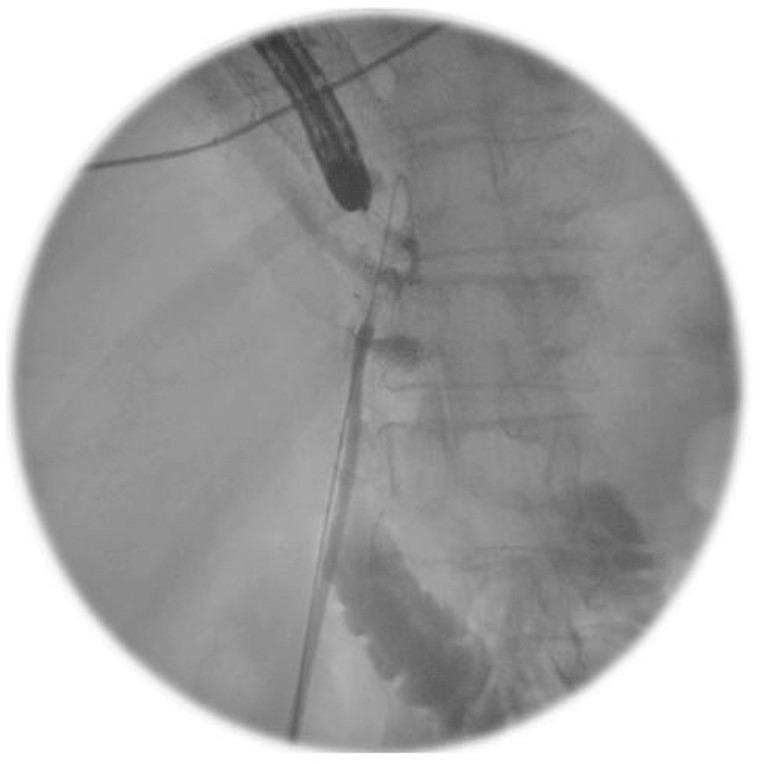

Management of upper gastrointestinal anastomotic leaks is an inter-disciplinary challenge. We present a case of late pyloroplasty leak following 3-stage oesophagectomy. We describe a novel, combined endoscopic and fluroscopic procedure to introduce a T-tube into the anastomotic leak proving an ideal plug at the site of leak which enabled the patient to consume a normal diet and return home safely.